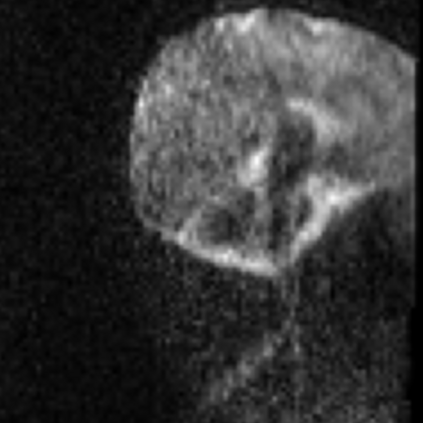

Assessing the severity of artifacts in pediatric brain Magnetic Resonance Imaging (MRI) is critical for diagnostic accuracy, especially in low-field systems where the signal-to-noise ratio is reduced. Manual quality assessment is time-consuming and subjective, motivating the need for robust automated solutions. In this work, we propose BRIQA (Balanced Reweighting in Image Quality Assessment), which addresses class imbalance in artifact severity levels. BRIQA uses gradient-based loss reweighting to dynamically adjust per-class contributions and employs a rotating batching scheme to ensure consistent exposure to underrepresented classes. Through experiments, no single architecture performs best across all artifact types, emphasizing the importance of architectural diversity. The rotating batching configuration improves performance across metrics by promoting balanced learning when combined with cross-entropy loss. BRIQA improves average macro F1 score from 0.659 to 0.706, with notable gains in Noise (0.430), Zipper (0.098), Positioning (0.097), Contrast (0.217), Motion (0.022), and Banding (0.012) artifact severity classification. The code is available at https://github.com/BioMedIA-MBZUAI/BRIQA.